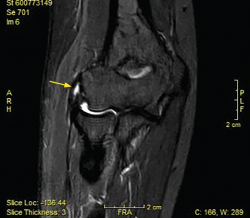

La resonancia magnética (RM) permite identificar cambios que incluyen el aumento de la señal del tendón dentro o alrededor de la inserción, engrosamiento del tendón o una discreta colección de líquido entre la cápsula lateral y el tendón extensor (Figura 8). La mayoría de los pacientes con síntomas de tendinopatía lateral crónica muestran cambios de señal en la RM y se ha podido relacionar la proporcionalidad entre la severidad de los cambios y la sintomatología del paciente(17). Ofrece ciertas ventajas frente al resto, como el hecho de que es más reproducible, reduce la variabilidad interobservador y ofrece más información acerca de la patología intraarticular(18). En ciertos entornos, sin problemas para obtener RM de calidad en periodos cortos de tiempo, se utiliza la RM para cuantificar el espesor de la lesión y la localización superficial o profunda de la misma y en función de dichos hallazgos planificar un abordaje abierto o artroscópico. En medios con dificultades para obtener RM en todas las sospechas de tendinopatía lateral de codo(19), la ecografía puede ser útil para diagnosticar de manera adecuada esta patología en la mayoría de los pacientes, lo que permite reservar la RM para pacientes con síntomas cuyos hallazgos ecográficos sean normales.(20).

Figura 8. Cambios vistos en resonancia magnética en paciente con dolor en la cara lateral del codo. Aumento de la señal del tendón dentro (flecha) o alrededor de la inserción, engrosamiento del tendón y una discreta colección de líquido entre el ligamento colateral lateral.